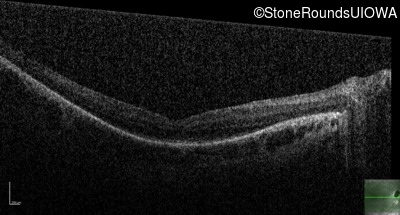

Optical Coherence Tomography - Right - 20/100 +1

Exemplar / OCT Stack

OCT Stack